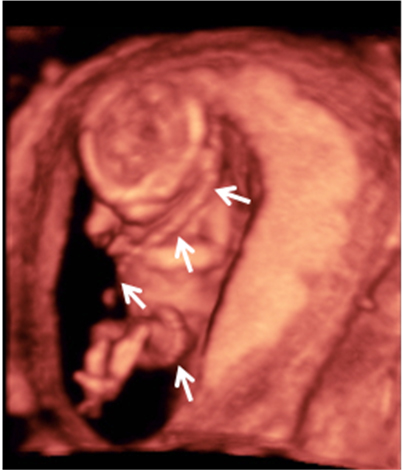

Ecografía semana 13: Bebé enrollado con su cordón umbilical

El cordón umbilical es una estructura gelatinosa que suele enrollarse alrededor del feto a medida que este se mueve, especialmente en el primer y segundo trimestre de embarazo. Son perfectamente visibles en las ecografías en 3D.

Feto con cordón umbilical enrollado al cuerpo

Vemos la imagen en tres dimensiones de un feto de 13 semanas de gestación. El cordón umbilical (indicado por las flechas) se asemeja un cinturón de seguridad, ya que pasa del hombro izquierdo a cadera derecha. Luego el cordón continúa por debajo de las piernas para insertarse en el ombligo del bebé.